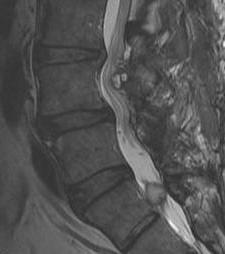

vert lymphoma 1vert lymphoma 2